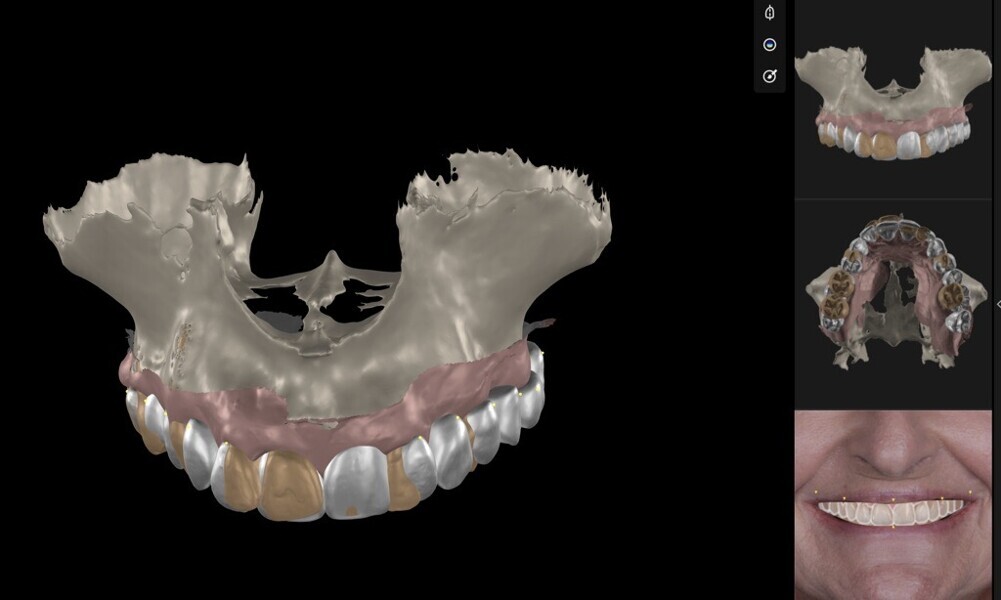

To ensure precise and predictable treatment planning, the DICOM files, STL files and clinical photographs were seamlessly integrated into Smilecloud, utilising advanced artificial intelligence technologies to deliver a highly personalised smile with exceptional precision (Figs. 11–15).

Figs. 11–15: DICOM files, STL files and clinical photographs were integrated into Smilecloud, leveraging artificial intelligence for precise, personalised smile design.

Fig. 12

Fig. 13

Fig. 14

Fig. 15